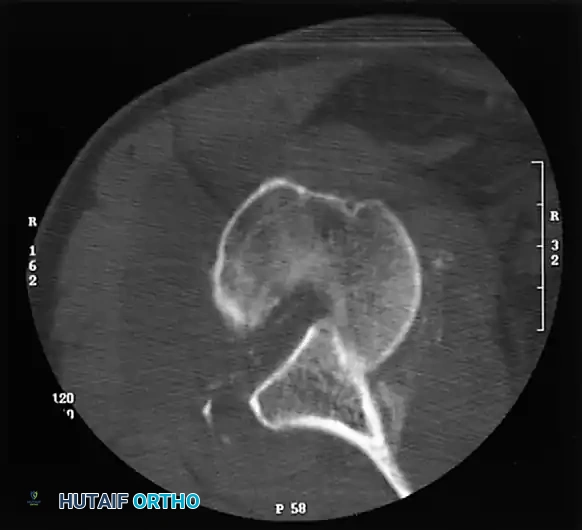

As emphasized by Kirtland et al., computed tomography (CT) with three-dimensional (3D) reconstruction is the definitive modality for evaluating bony injuries. CT accurately quantifies the percentage of articular surface damage on the humeral head, which is the primary determining factor in selecting the appropriate surgical intervention.

In chronic anterior dislocations, the posterolateral aspect of the humeral head is driven against the sharp anterior rim of the glenoid. This constant impingement produces a massive compression fracture. Because the patient repeatedly attempts to mobilize the joint, this defect is typically much larger and deeper than the classic Hill-Sachs lesion seen in recurrent, acute anterior instability.

Concurrently, the anterior glenoid rim suffers compression fractures, and in long-standing cases, a false joint or "pseudoarticulation" forms between the humeral head and the anterior scapular neck.

Chronic posterior dislocations produce a reverse Hill-Sachs lesion—a large compression fracture on the anteromedial aspect of the humeral head caused by impingement against the posterior glenoid rim. Similar to anterior variants, these defects enlarge over time due to the patient's continual, forceful attempts to increase their range of motion.

Osseous Pathology

Bony architecture is progressively destroyed by the persistent abnormal articulation.